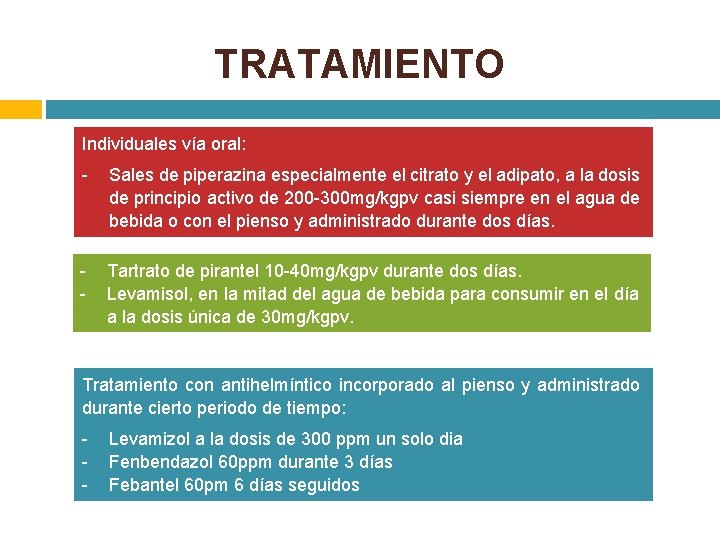

TRATAMIENTO Individuales vía oral: - Sales de piperazina especialmente el citrato y el adipato, a la dosis de principio activo de 200 -300 mg/kgpv casi siempre en el agua de bebida o con el pienso y administrado durante dos días. - Tartrato de pirantel 10 -40 mg/kgpv durante dos días. Levamisol, en la mitad del agua de bebida para consumir en el día a la dosis única de 30 mg/kgpv. Tratamiento con antihelmíntico incorporado al pienso y administrado durante cierto periodo de tiempo: - Levamizol a la dosis de 300 ppm un solo dia Fenbendazol 60 ppm durante 3 días Febantel 60 pm 6 días seguidos